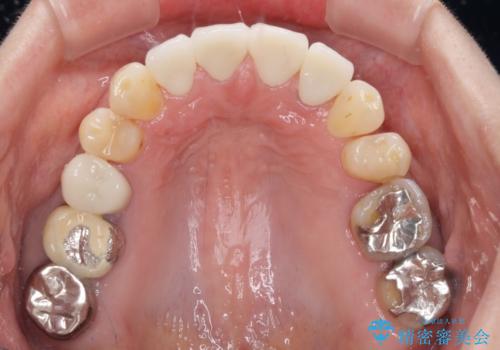

目立つ範囲である前歯4歯をオールセラミッククラウンにて補綴することとしました。

口元の印象が明るくなり、人前で気にせずに笑えるようになりました。